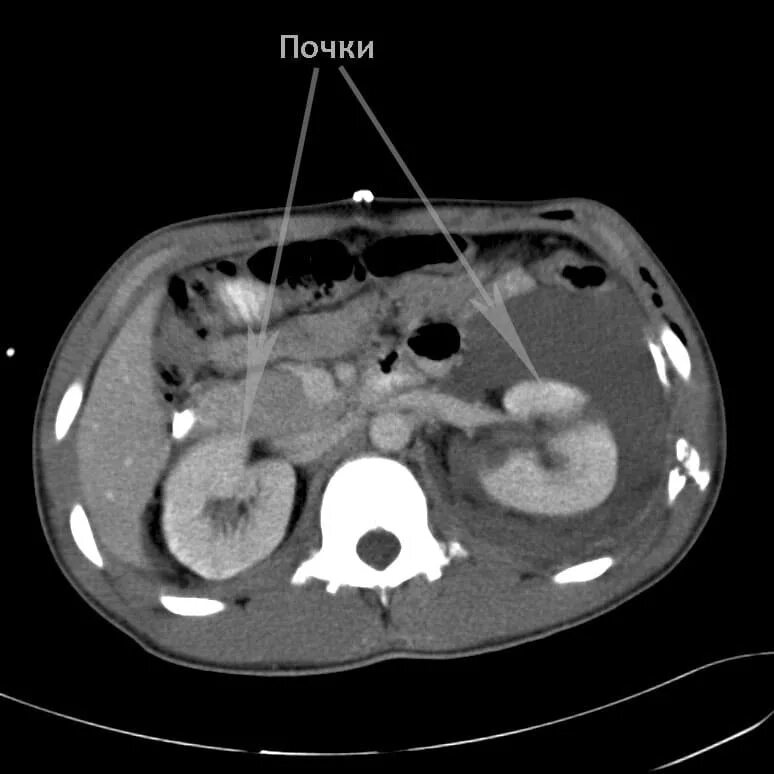

Как подготовиться к кт с контрастом почек